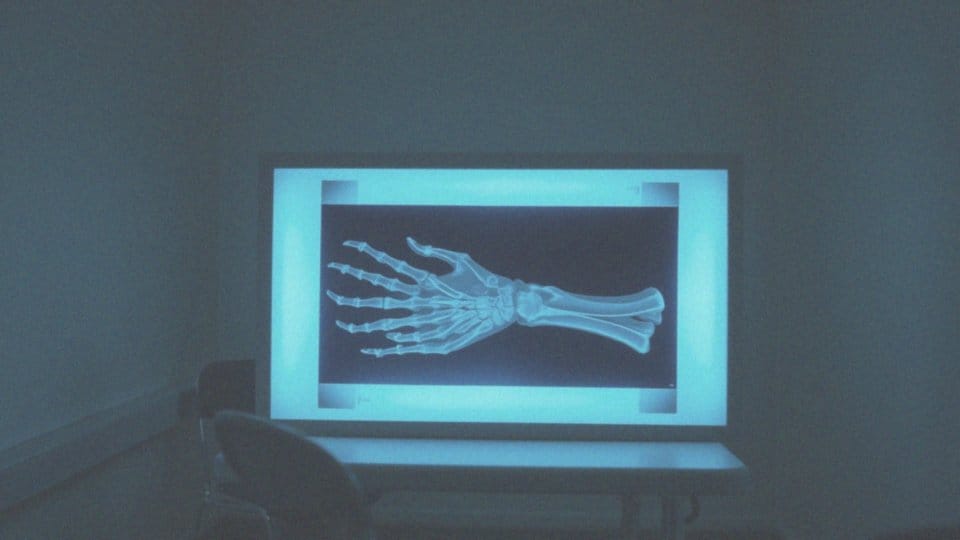

W diagnostyce istotną rolę odgrywa badanie RTG. Dzięki niemu można wykryć nawet te złamania, które mogły umknąć podczas wcześniejszych badań. Takie podejście pozwala na dokładniejszą ocenę stopnia uszkodzenia.

Jak diagnostyka RTG pomaga w ocenie złamania?

Diagnostyka rentgenowska pełni niezwykle istotną rolę w analizie złamań kości. Badania RTG umożliwiają szczegółowe ukazanie zarówno wad, jak i charakterystyki złamań, co jest niezbędne dla efektywnego leczenia. Dzięki tym przedstawieniom lekarze są w stanie dokładnie określić rodzaj złamania. Może to być na przykład:

- złamanie poprzeczne,

- skośne,

- spiralne,

- kompresyjne,

- wieloodłamowe,

- segmentowe.

Kiedy mowa o szczelinie złamania, badanie rentgenowskie pozwala na ocenę lokalizacji pęknięcia oraz stopnia przemieszczenia fragmentów kostnych. Co więcej, RTG ma zdolność ujawnienia wcześniejszych, często pomijanych urazów. Widoczna szczelina na zdjęciach rentgenowskich sygnalizuje konieczność przeprowadzenia dalszych badań, aby uzyskać pełniejszy obraz stanu zdrowia pacjenta. Dodatkowo, technika ta wspiera diagnozowanie ewentualnych innych patologii, takich jak uszkodzenia tkanek miękkich czy zapalenia. Wyniki analiz RTG wspomagają lekarzy w podejmowaniu decyzji odnośnie do kolejnych kroków w leczeniu oraz rehabilitacji. To z kolei przyspiesza i precyzyjnie określa ścieżkę terapeutyczną, co ma ogromne znaczenie dla uniknięcia długotrwałych problemów zdrowotnych.